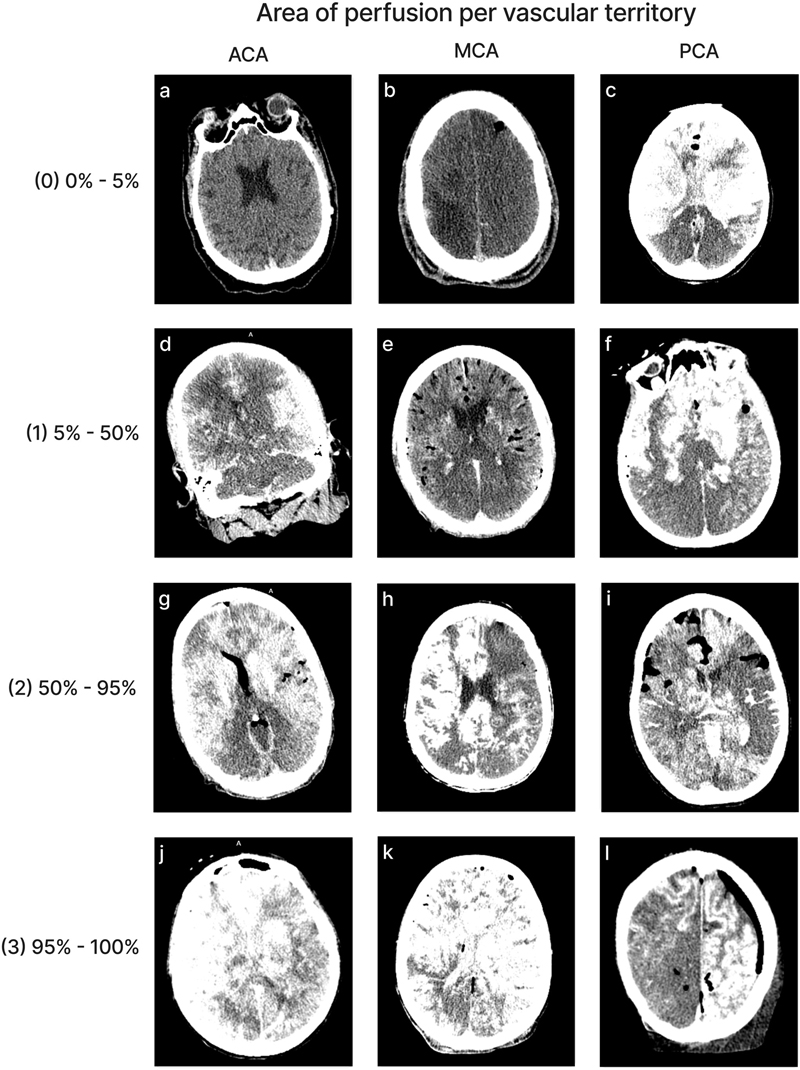

CT images

We aimed to perform neuroimaging both before and after perfusion, with the brain remaining inside of the skull. The CT scanner we used was the OmniTom® Elite (Neurologica, Danvers, MA), a 16-slice scanner. Images were viewed with the Osimis Web Viewer. Occasionally, one or both of these CT scans was not performed, for example if the CT scanner was not working at the time. For each of eight major vascular territories – corresponding to the territory supplied by the left and right anterior cerebral artery (ACA), middle cerebral artery (MCA), and posterior cerebral artery (PCA), as well as the cerebellum, we graded the extent of contrast visualized on the post-perfusion CT scans in a given territory on a 0–3 scale, with 0 indicating < 5 % extent of perfusion, 1 indicating 5–50 %, 2 indicating 50–95 %, and 3 indicating > 95 %. In some cases, the grades could not be completed for some of the areas in the brain because the available CT scan contained only part of the brain, not the whole brain. The extent of air bubbles in the CT scan across the brain was also graded on a 0–3 scale, with 0 indicating no apparent air bubbles, 1 minimal, 2 moderate, and 3 substantial. This grading was performed on all of the post-perfusion CT scans available via the collaboration of two graders. For a brain-wide assessment measure, we generated a separate score based on the sum of the grades across all evaluated areas, excluding cases with missing data from any vascular territory.

We developed a semi-quantitative rating scale to measure the extent of tissue perfusion in areas corresponding to each of six major cerebral arteries (i.e. the left and right anterior cerebral artery, middle cerebral artery, and posterior cerebral artery), as well as both sides of the cerebellum. Perfusion quality was assessed based on degree of pallor, clearance of surface blood vessels, visible tissue stiffness, and the presence of colored dye when used at a concentration sufficient for visualization (Figure 2). For a subset of data, perfusion quality based on these images was graded separately by two independent raters. These grades had an ICC of 0.691 (95 % CI 0.542–0.799), indicating good interrater reliability. Qualitatively, we found that in nearly all cases, perfusion appeared patchy achieved across the surface of the brain – both between and within vascular territories, for reasons that remain unclear.

Representative gross examination images showing perfusion rated to be each of the four grades (0, 1, 2, and 3) with in the vascular distributions of the anterior cerebral artery (ACA), middle cerebral artery (MCA), and posterior cerebral artery (PCA). For grade 0, we did not have a single brain with a grade of 0 in all three regions, so different brain samples were used for each representative image. Donor IDs: 169 (a), 183 (b, c), 205 (d, e, f), 197 (g, h, i), 126 (j, k, l).

Quality of perfusion in CT images

Perfusion quality based on CT scans was graded on a semi-quantitative scale, reflecting the estimated percentage of contrast agent present in different brain regions (Figure 4). We also developed a semi-quantitative grading scale to assess the extent of air bubbles observed in some CT scans (Figure 5). For a subset of cases, the images were graded separately by two independent raters, yielding an ICC of 0.536 (95 % CI: 0.293–0.705), indicating fair interrater reliability. Consistent with the observations from gross examination images, the CT scans revealed patchy distribution of contrast in nearly all cases, both across and within vascular territories.

Figure 4.

Representative images of CT scans that demonstrate the grading schema. All images show the grading for both the left and right sides of the respective region, except for image(l), in which only the left side represents the correct grading. Images follow the standard radiological convention, with the right side of the image corresponding to the donor’s left side and vice versa. Donor IDs: 136 (a), 71 (b), 185 (c), 179 (d), 197 (e), 201 (f), 195 (g), 5 (h), 84 (i), 203 (j), 206 (k), 142 (l).

The mean perfusion quality grades based on CT scans across both hemispheres were 1.94 ± 0.09 for the ACA distribution, 1.80 ± 0.09 for the MCA, 1.33 ± 0.09 for the PCA, and 1.32 ± 0.07 for the cerebellum (Figure 6). There was no significant difference between the grades in the ACA and MCA distribution (t-test p-value = 0.27). The grades in the ACA and MCA were each significantly higher than those in the PCA (t-test, p-values = 2.6e-6 and 0.0003, respectively) and the cerebellum (t-test, p-values = 2.3e-7 and 6.8e-5, respectively). Therefore, as with the gross examination data, average perfusion quality graded on CT scans was found to be higher in the regions supplied by the anterior circulation than in those supplied by the posterior circulation.